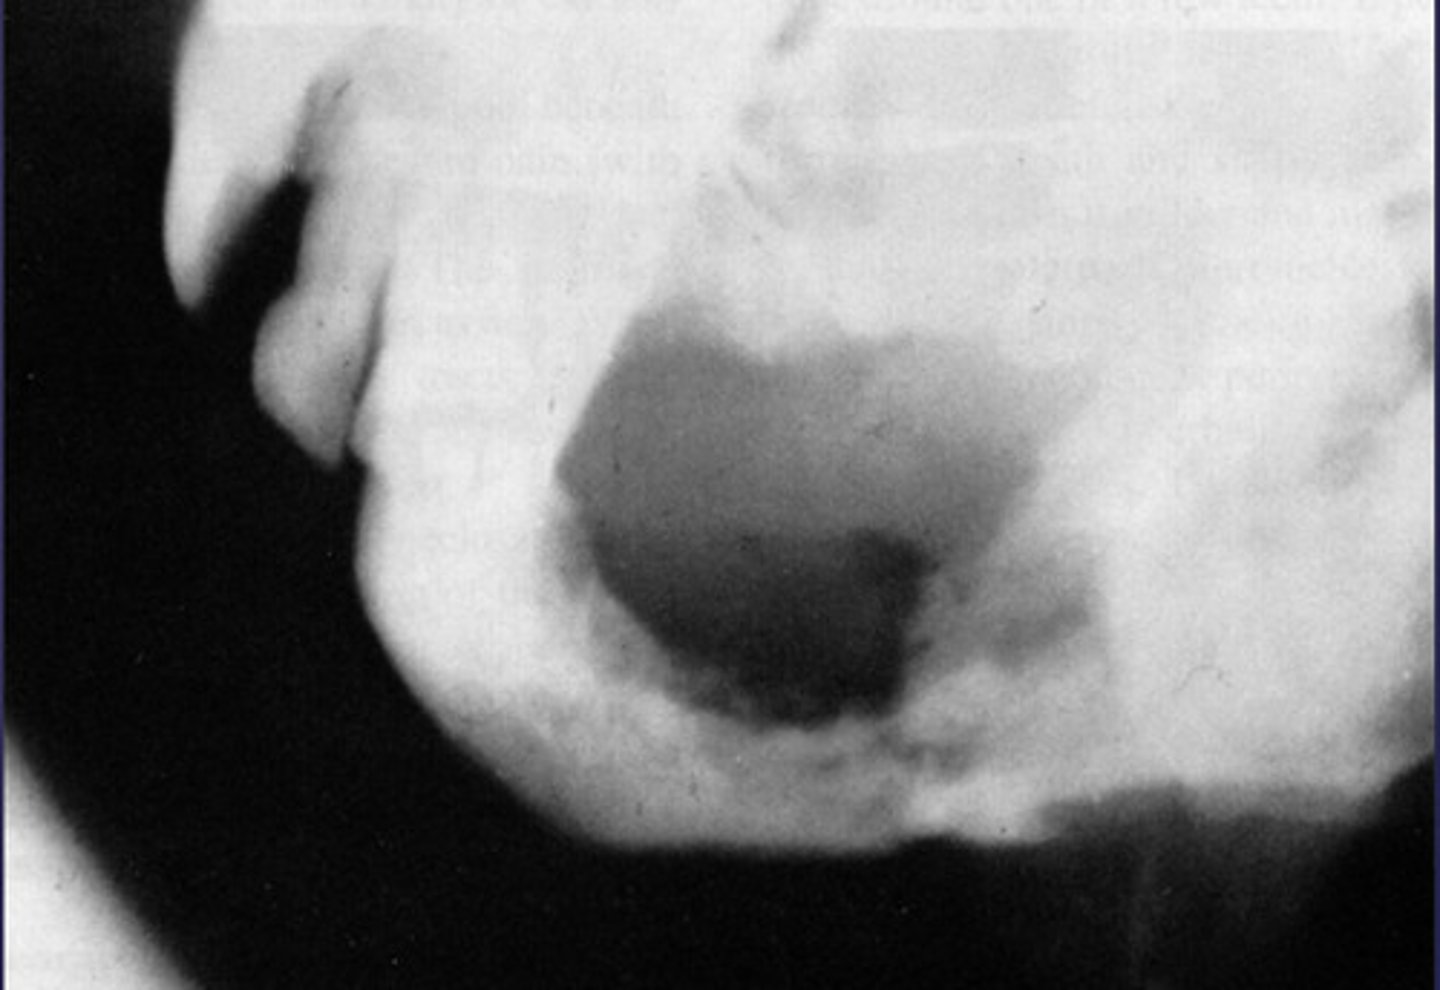

How would you describe the lesion?

- Well-defined corticated unilocular radiolucency in the left ramus causing expansion and thinning of

anterior and posterior walls of ramus, inferiorly below the inferior mandibular cortex and the coronoid process

- Dispalcement of the developing third molar.

What category would this lesion be part of?

Benign

What would be included in your D/D?

- OKC

- Unicystic ameloblastoma

- Dentigerous cyst